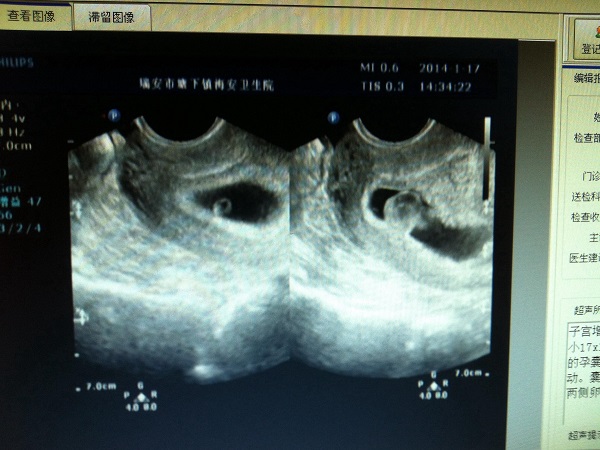

2022孕囊尺寸对照表来了,孕6周大小不能低于这个数

孕囊其实就是原始的胚盘组织,是被羊膜和血管所包裹住的一个小胚胎,是胚胎最初的形态。一般来说,随着孕周的逐渐增加孕囊的大小也在发生变化,在女性怀孕6周的时候,孕囊..

各阶段孕囊大小都有对照表,50天时尺寸不能低于这个标准

宫腔内检查出孕囊是怀孕的标志,孕囊的大小会随着怀孕时间的增加逐渐变大,然后孕囊里面会长出胎芽,然后再发育成胚胎。一般来说怀孕50天的时候孕囊的大小在1.33cm左右,但..

怎么从孕囊的尺寸来辨别胎儿的性别?

从孕囊长宽尺寸大小不能看男女。孕囊的形状是由其张力及其可伸展的空间来决定,一般发育较好的孕囊是扁圆形的,但是有时孕囊会随宫腔的形状而变长,孕囊的形状由其张力和含..

b超单子怎么看男女宝宝最准确的结果?孕囊尺寸怎么看男女性别?

虽然现在对于男女性别都没有那么看重,但是依然还是会有好多的人,都会根据b超检查单子上面的数据显示来判断预测胎儿的男女性别。那么,b超单子怎么看男女宝宝最准确的结果..